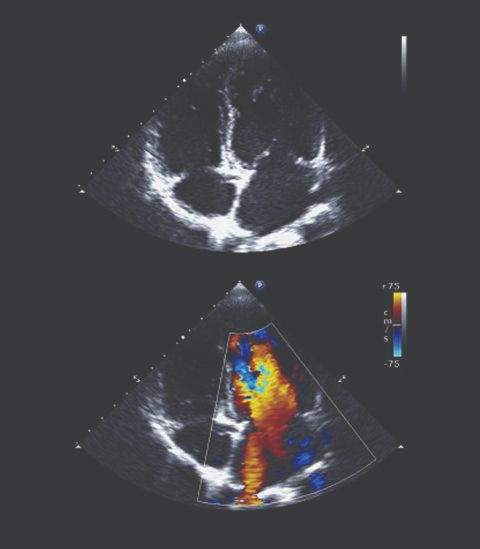

UZV srca je dijagnostička pretraga kojom se dobije informacija o stanju srčanog mišića, eventualnim zadebljanjima ili defektima usljed preboljelog infarkta.

Također se korištenjem doplerske tehnike do...